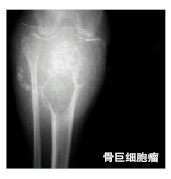

骨巨细胞瘤

诊断

NCCN指南推荐的诊断检查包括病史采集、体格检查、充分的影像学检查(X线、CT和MRI)。胸部X线和CT检查对于发现肺转移灶很重要,对于某些特殊的病例,可考虑行骨扫描检查。活检对于确诊是必不可少的。

blob.png

治疗

对于可切除病例,最主要治疗方式是囊内刮除,可根据需要选择是否辅助其他治疗。在一些临床研究中,系列动脉栓塞治疗效果显著,特别是对皮质破坏较严重、关节受累或骶骨的巨大骨巨细胞瘤。一项关于人源化抗RANK配体单克隆抗体地诺单抗的Ⅱ期临床研究显示,对于不能切除或复发的骨巨细胞瘤,地诺单抗治疗可获得非常好的肿瘤反应,即消灭90%以上的巨细胞,或超过25周影像学表现无进展,总反应率为86%。

建议  对于可切除的病例首选切除;但对于不可切除的中轴骨病变,或虽可切除但切除后会发生不可接受的病残率的病例,推荐进行非手术治疗(包括系列栓塞、地诺单抗、干扰素或聚乙二醇干扰素)。因放疗有增加恶变的风险,所以只用于那些不能应用栓塞、地诺单抗和干扰素治疗的病例。

对于非手术治疗后获得稳定或改善的病例,下一步可选择继续观察;若仍没有治愈但已转变为可切除的病例,应选择囊内切除,而对仍不能切除者应继续予地诺单抗治疗。若疾病进展,可反复使用推荐的几种非手术治疗方法。

对于已发生转移的病例,对其原发病灶的处理与没有转移的病例相同。对于可切除的转移病灶,应选择囊内切除;对于不可切除的转移病灶,地诺单抗、干扰素或聚乙二醇干扰素、放疗或观察均可作为选择。